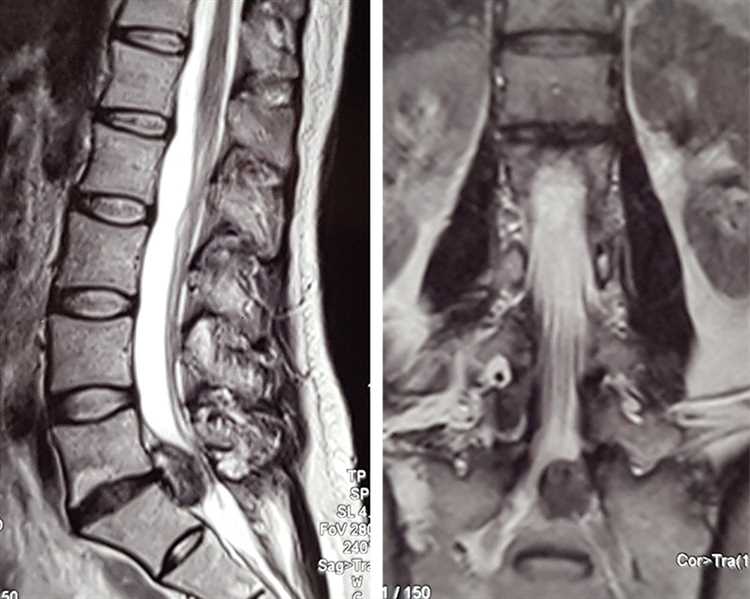

Врачи отмечают, что медикаментозная терапия при грыже может быть эффективной в определенных случаях, особенно на начальных стадиях заболевания. Основная цель лечения заключается в снятии болевого синдрома и уменьшении воспалительных процессов. Использование нестероидных противовоспалительных средств (НПВС) и миорелаксантов позволяет пациентам значительно улучшить качество жизни. Однако специалисты подчеркивают, что медикаменты не устраняют саму причину грыжи и не могут заменить хирургическое вмешательство в более запущенных случаях. Врачи рекомендуют комплексный подход, включая физическую терапию и изменение образа жизни, чтобы достичь наилучших результатов. Важно, чтобы лечение проводилось под контролем специалиста, что позволит избежать осложнений и улучшить прогноз для пациента.

Можно ли медикаментозно вылечить грыжу позвоночника?

В лечении грыжи диска позвоночника, особенно при наличии острого болевого синдрома, используются медикаментозные методы лечения. Противовоспалительные препараты (НПВП): аспирин, ибупрофен или напроксен.

Как эффективно лечить межпозвоночную грыжу?

Грыжа межпозвоночного отдела лечится, как правило, хирургически. На начальных этапах прогрессирования заболевания используется консервативная (безоперационная) терапия. Медикаментозное лечение может продлиться несколько месяцев, но весь курс дает неплохие результаты.